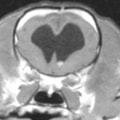

正常な脳室

拡張した脳室